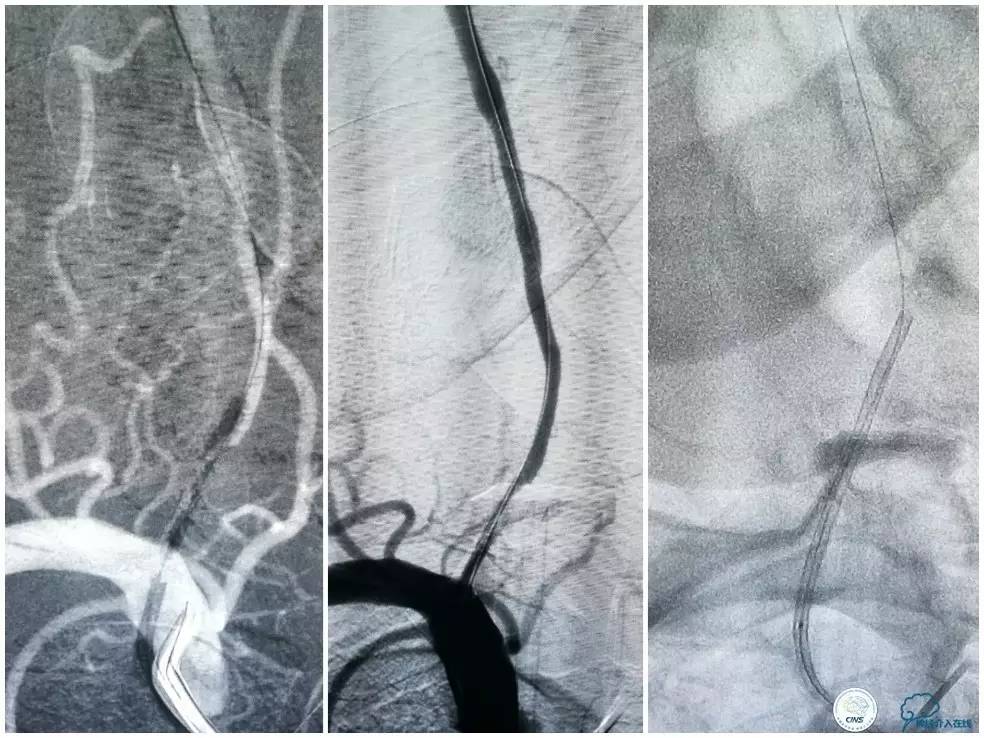

此时多体外投照显示右椎V4-基底动脉极重度狭窄,几近闭塞(图12)。

图12

Transend(0.014″300cm)微导丝+Echelon-10微导管,小心通过右椎动脉V4段病变后置于右大脑后动脉P1段(图13)。

图13

Gateway球囊(1.5mm×15mm)于狭窄段扩张后放置Wingspan支架(2.5 mm×15mm),撤出微导丝后造影,局部狭窄率50%,支架内中远段见细小充盈缺损,考虑急性血栓形成,予以欣维宁5ml动脉内缓慢注射未见好转(图14)。

图14